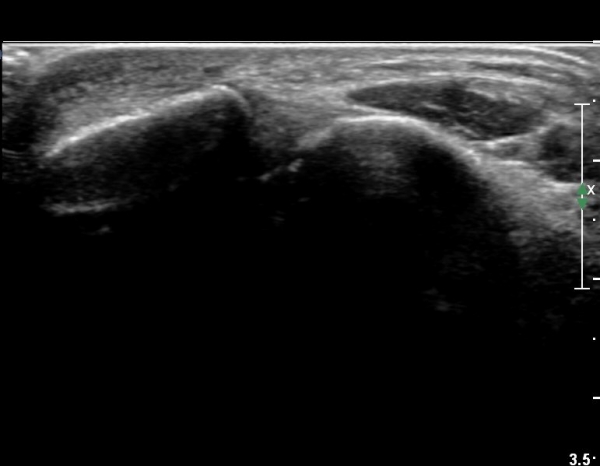

Àü°ÅºñÀÎ´ë ºÎÇϰ˻翡¼­ ÀδëÆÄ¿­ ºÎÀ§°¡ ¹ú¾îÁö°í °Å°ñÀÌ ¾ÕÀ¸·Î ´Ü°ÜÁö´Â ¼Ò°ßÀ» º¸ÀÓ(»çÁø 3, 4, ÷ºÎ µ¿¿µ»ó).